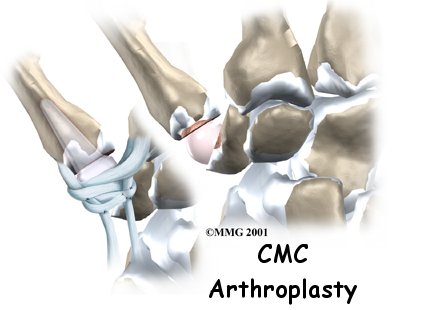

Artificial Joint Replacement of the Thumb - FYZICAL Grove City's Guide

If nonsurgical treatments are not successful in easing problems of thumb arthritis, your doctor may recommend replacing the surfaces of the joint. Joint replacement surgery is called arthroplasty.

Excision Arthroplasty of the Thumb

Thumb arthritis may be surgically treated with a procedure called excision arthroplasty. The term excision means to take out. In this surgery, the surgeon takes out a small bone at the base of the thumb and fills in the space with a rolled up section of tendon. The soft tissue forms a false joint that keeps the thumb somewhat mobile and stops pain by preventing the joint surfaces from rubbing together.